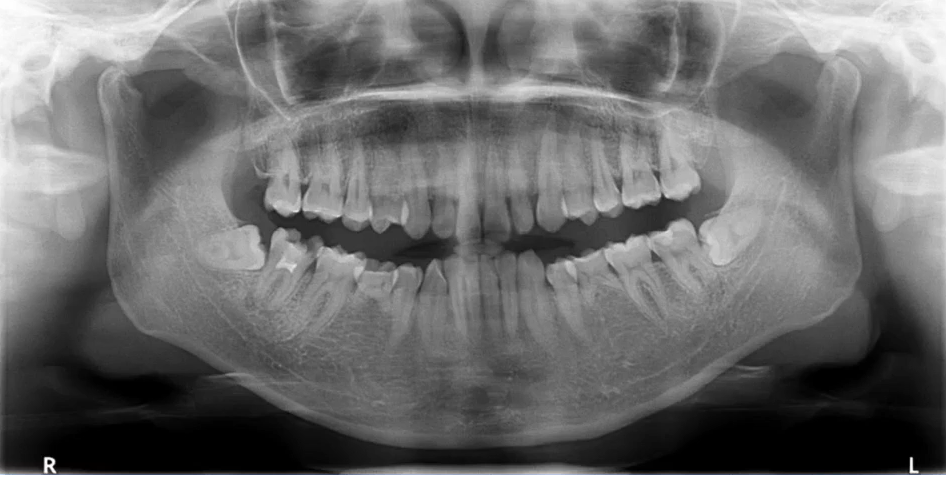

中线左右对称,牙齿排列呈微笑弧形,片子左右两边相对对称,能清晰显示颞下颌关节、上下牙列的牙根,图像的对比度和分辨率较好。

因为曲面断层片反映的是上下颌牙齿、上颌窦、关节,在一张片子中所展示的解剖结构较多。比如刚才的片子,最容易诊断的是右下6远中邻面深龋合并根尖周炎,左下有埋伏的多生智齿,右侧是垂直智齿。

注意不要遗漏,比如片子中显示上颌两个3是缺失的,是先天性缺失还是做过手术?有可能会漏掉一些临床信息。

2. 推荐象限顺序

1(右上)→2(左上)→3(左下)→4(右下)

3. 推荐检查部位顺序

牙→骨→上颌窦→关节